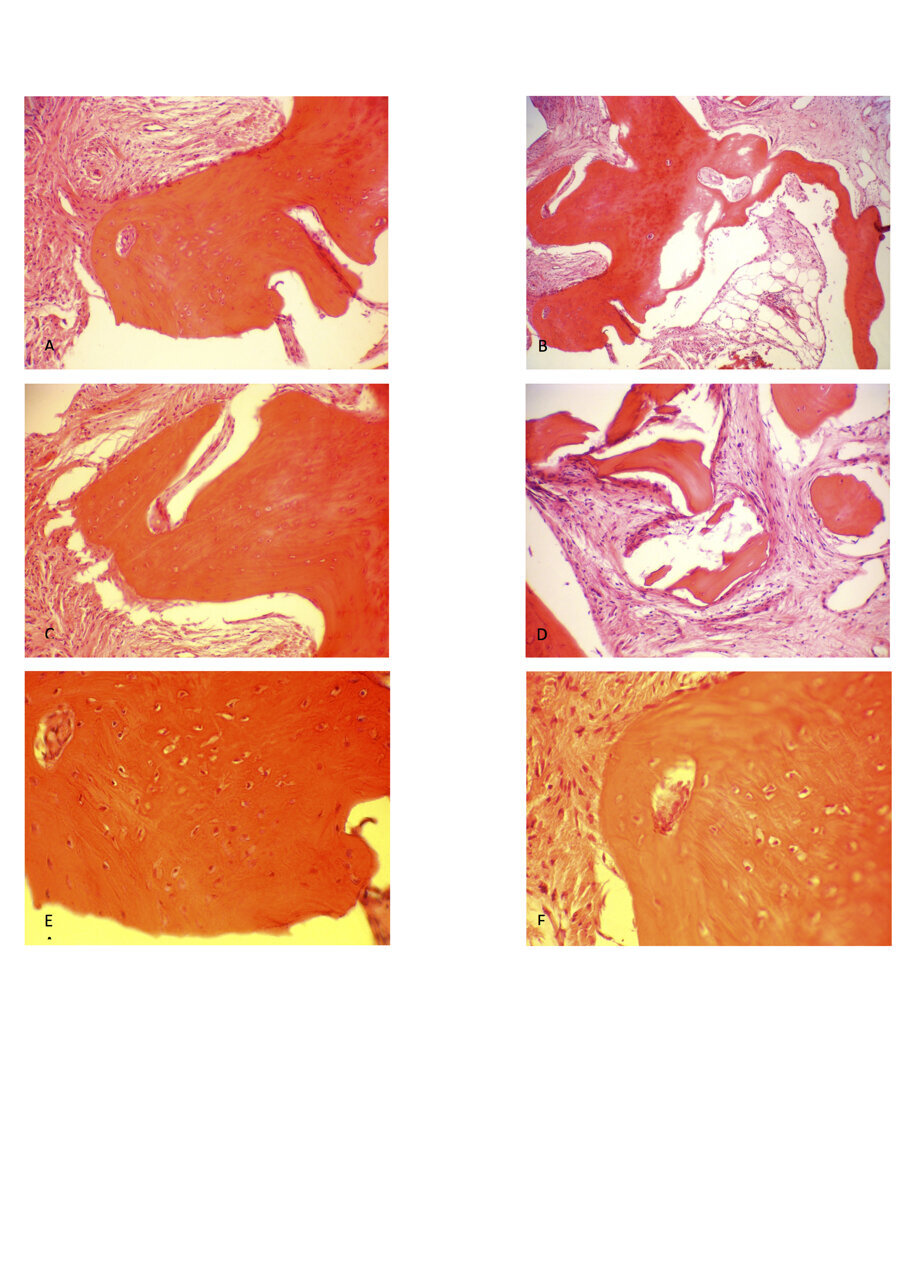

La radiografia eseguita immediatamente dopo il posizionamento dell’impianto ha mostrato che gli impianti dentali erano perfettamente posizionati a livello dell’osso crestale (Fig. 6). Le analisi istologiche della carotatura di osso prelevato hanno mostrato che a 6 mesi dall’intervento di conservazione dell’alveolo, si è formato nuovo tessuto osseo vitale e sono ancora presenti granuli del biomateriale utilizzato (Fig. 12). Il follow up radiografico a 3 anni indica una situazione ossea invariata con l’impianto ancora a livello dell’osso crestale. La parte protesica ancora in buone condizioni senza segni d’infiammazione, né si sono riscontrate mucositi o perimplantiti. I restauri privi di complicanze tecniche.

Dal punto di vista istologico, è stato trovato osso vitale neoformato; inoltre, granuli dello xenoinnesto bovino erano ancora presenti. Questi risultati, se confrontati con lo studio di Barone et al. 201326, dove è stato utilizzato osso bovino termicamente deproteinizzato come materiale di riempimento per la chirurgia GBR dopo l’estrazione del dente, hanno mostrato che dopo sei mesi era presente una maggiore quantità di osso vitale e una minore quantità di granuli di biomateriale. Ciò è probabilmente dovuto al fatto che il processo di decellularizzazione del materiale utilizzato in questo studio, chiamato Thermagen, utilizza temperature più basse, quindi le particelle del biomateriale non sono cristalline, permettendo agli osteoclasti di degradarle facilmente e lasciando spazio al nuovo osso formato.

In letteratura, molti studi clinici presentano evidenze istomorfometriche a favore del riempimento immediato dell’alvelolo post-estrattivo con osso bovino termicamente deproteinizzato, con intervallo di guarigione di 6 mesi come in questo studio28, 29. L’osso vitale neo formato aveva varianza tra il 34,5% e il 39,4% che visivamente confrontato con l’istologia del nostro studio, sembra essere molto meno.